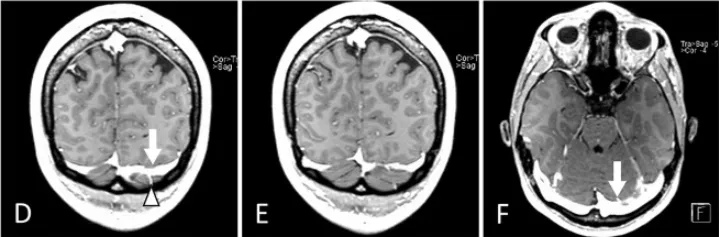

增强T1加权磁共振成像(冠状位D、E,轴位F):左侧优势静脉窦及桥静脉;据此选择静脉窦穹隆更高的右侧入路。